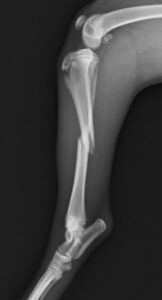

落下事故で右足の脛を骨折したワンちゃんが来院されました。ロッキングプレートであるMATRIX2.5と2.4スクリューで手術し、無事元気に歩いて退院していきました。よかったね。